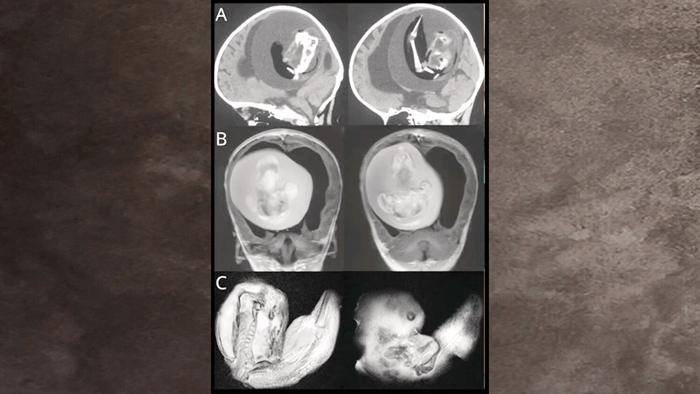

Hindistan'da 1 Şubat'ta doğan bebek, karnında gelişen ikizinin fetüsüyle dünyaya geldi. Doktorlar, gelişimini tamamlayamayan fetüsü bebeğin karnından başarıyla çıkardı. Dr. Prasad Agarwal, "Bu, dünyanın en nadir vakalarından biri" dedi. 32 yaşındaki anne ve bebeğin sağlık durumunun iyi olduğu açıklandı.

Uzmanlar, içeride gelişen diğer fetüsün hayatta kalamayacak kadar az gelişmiş olduğunu söyledi. Doktorlar bunun tek bir döllenmiş yumurtanın bölünmesi sırasında tam ayrılmamasından kaynaklandığını belirtiyor. Literatürde 'fetus in fetu' olarak adlandırılan olayın dünyada yalnızca 200 kez yaşandığı açıklandı.

'Fetus in fetu' vakasında; bir fetüs anne karnında gelişirken, ikizini de içinde büyütmeye devam ediyor.

Benzer bir olay geçen yıl Çin'de meydana gelmişti. Yapılan incelemede, 1 yaşındaki kız çocuğun beyninde 'doğmamış ikizinin fetüsünü' bulunmuştu. Kardeşinin içindeyken aylarca büyümeye devam eden 5 santim uzunluğundaki fetüs, kızın kafası büyüdüğü ve motor becerilerinde sorunlar yaşadığı zaman ortaya çıkmıştı.